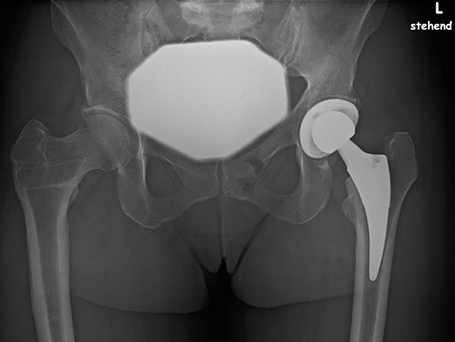

HÜFT-TEP DER PATIENTIN

Linksseitige Coxarthrose, nach Umstellungsosteotomie rechts

Planung Hüft-Endoprothese links

Nach Implantation einer Kurzschaftprothese auf der linken Seite. Die rechte Seite nach Umstellungsosteotomie vor Jahren